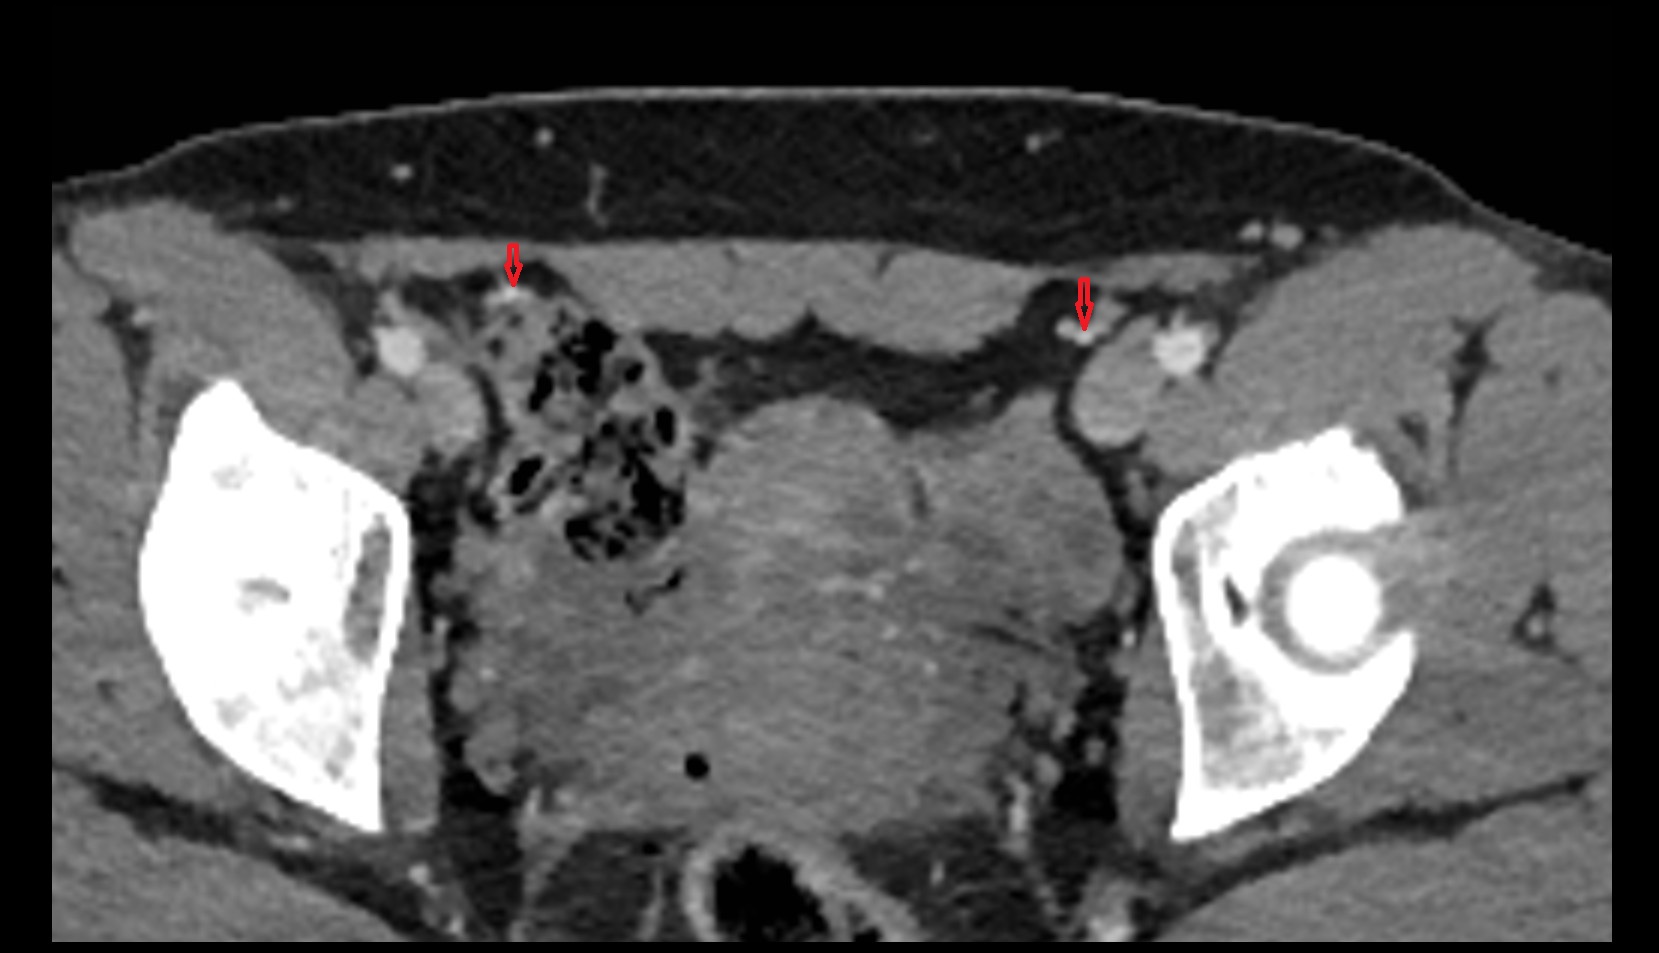

- Inguinal lymph nodes

- External iliac lymph nodes